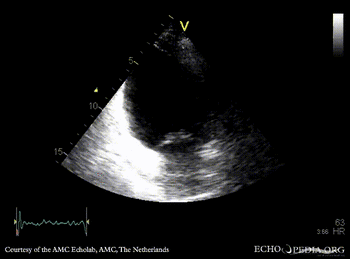

Infarction of posterior and inferior wall

PLAX: dilated left ventricle, akinesia of posterior wall PSAX: akinesia of posterior and inferior wall